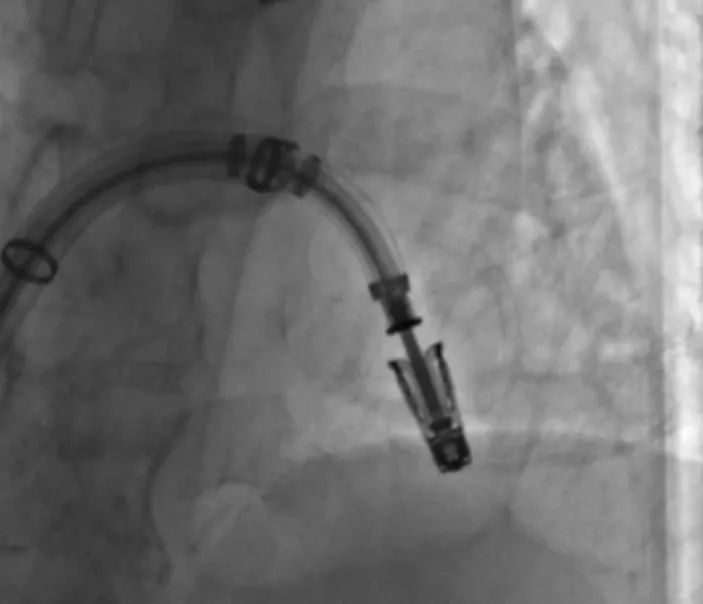

患者术后TEE提示二尖瓣反流显著减轻,瓣膜夹位置和功能良好(图4-5)

手术采用经典股静脉-房间隔入路,房间隔穿刺后将瓣膜夹输送系统送入左心房,在TEE引导下捕捉二尖瓣前后瓣叶,并关闭瓣膜夹。经TEE反复确认手术效果后最终释放瓣膜夹。术中仅植入一枚JensClip瓣膜夹就达到了良好的治疗效果,术后即刻心超二尖瓣反流减少到0-1+,瓣膜夹位置稳定,功能良好。术后患者症状明显好转,术后复查TTE反流0-1+,瓣膜夹位置稳定,拟于近期出院。